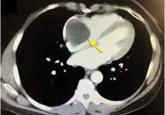

A woman with a history of endometrial adenocarcinoma presented with occasional shortness of breath and dizziness.